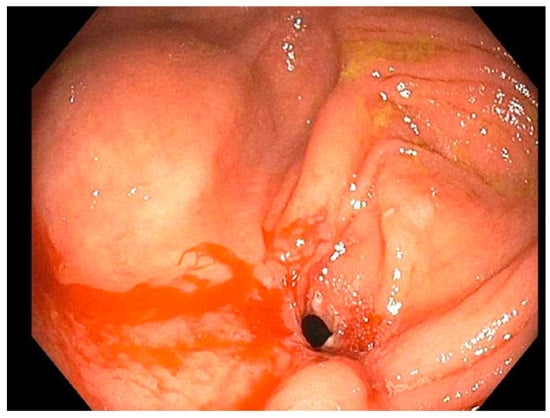

| 1 | (2019: Remicade 10 mg) (2019: Humira 40 mg) (2020: Humira 80 mg subcutaneous) | November 2019, dilated (b) TI from (12 to 18 mm) (a) TI stricture dilated to (16.5 mm) | November 2020, dilated TI to (20 mm) | March 2023, laparoscopic assisted ileocecectomy |

| 2 | (2019: prednisone 40 mg) (2019: Remicade 5 mg) (Remicade 10 mg) | September 2019, ICV dilated from (8 to 11 mm) | December 2020 and August 2021 ICV dilated from (9 to 18 mm) then (12 to 18 mm) | June 2022, ICV dilated from (13.5 to 20 mm) |

| 3 | (2019: prednisone 20 mg BID w/mesalamine 500 mg TID) (2020: 6-MP 50 mg) (2021: Humira 40 mg/MTX 25 mg) | February 2021, PAC dilated from (7 to 15 mm) | August 2021, PAC dilated from (15 to 20 mm) | August 2022, mucosal narrowing stretched to 20 mm without noted renting |

| 4 | (2021: Humira 40 mg every other week/steroid 40 mg daily, escalated to Humira 40 mg weekly) (2022: MTX 25 mg) | September 2022, dilation of the ICV from (4 to 13.5 mm) (food bezoar noted) | November 2022, ICV dilated from (8 to 15 mm) | December 2022, ICV dilated (12 to 15 mm) |